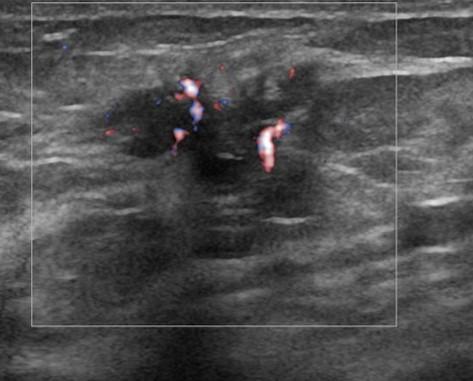

Ung thư vú

» Thông tin: Nữ giới – 52 tuổi.

» Lâm sàng: Khối tuyến vú.